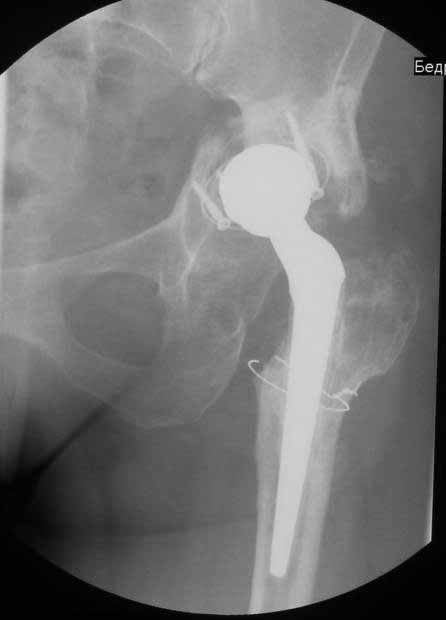

Пациентка 45 лет. Бесцементное эндопротезирование левого тазобедренного сустава 6 лет назад (впадина RM, Mathys, металл-металл, ножка Зульцеровская). За 10 лет до протезирования – коррегирующая остеотомия бедренной кости, которая не срослась в течение года до удаления пластины, а затем срослась в течение 3 месяцев иммобилизации в кокситной повязке. После протезирования получилось наблюдать пациентку почти постоянно, поскольку через 2 года синтезировал ей лодыжки на оперированной стороне, затем, через несколько месяцев удалил фиксаторы, а в 2009г. резецировал мениск на противоположной стороне. Боли все эти годы не беспокоили. Пациентка чуть выше среднего роста, вес тела нормальный. Физические нагрузки переносила хорошо. Работает на 7 этаже без лифта. Год назад экстирпация матки по поводу лейомиомы больших размеров. Несколько месяцев назад появились боли в области левого тазобедренного сустава. При рентгеновском и КТ исследованиях (июль с.г.) – нестабильность тазового компонента. От предложенной замены протеза пациентка на тот момент, слава богу, отказалась. Через какое то время боли в области левого тазобедренного сустава практически полностью прошли, а около 2 месяцев назад появилось ощущение патологической подвижности таза и боли в паху справа, которые через некоторое время уменьшились, а потом снова усилились после значительных физических нагрузок (много ходила по песку на пляже, носила тяжести). Ежедневно принимала диклофенак. На рентгенограммах – переломы правой лонной кости. Сейчас госпитализирована из-за болей в паху справа. Боли слева не беспокоят. На фоне снижения нагрузок в стационаре боли значимо уменьшились. Способна ходить без средств дополнительной опоры.

На представленных снимках тазобедренный сустав до и сразу после операции, затем 2 снимка 2009г., когда ничего не беспокоило, затем КТ 2-х месячной давности и вчерашние рентгенограммы обоих тазобедренных суставов.